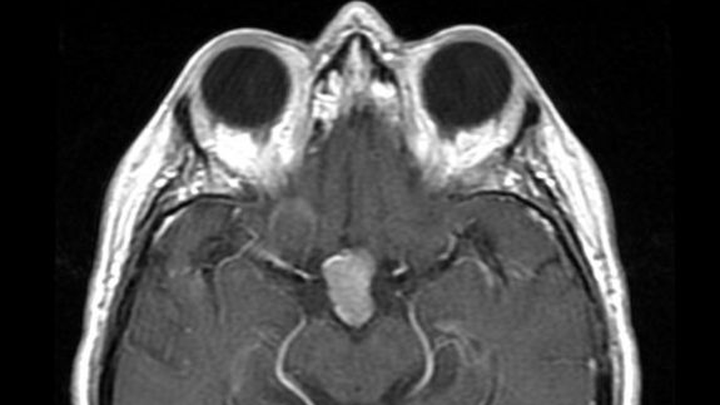

KC is currently undergoing Radiation Therapy three times a week to shrink her growing brain tumors. In April 2025, we found out that the tumor on Kc’s pituitary gland had grown from 2.3 cm to 10.5 cm. Due to her tumor being larger than 2.0 cm, Kc is ineligible to receive a Transnasal Transsphenoidal Surgery (less invasive surgery that removes brain tumors via the nose versus removal directly through the cranium). Kc silently continues to struggle mentally, physically, and financially, always placing others and their needs and wants above her own. Medication management and Radiation Therapy to shrink her tumors were recommended as the best modality of treatment. Unfortunately, Kc is not responding to treatment as doctors had hoped. Kc will need to undergo brain surgery once Radiation Treatment ends (last Radiation Treatment date: September 5, 2025) to remove the tumors from her brain.